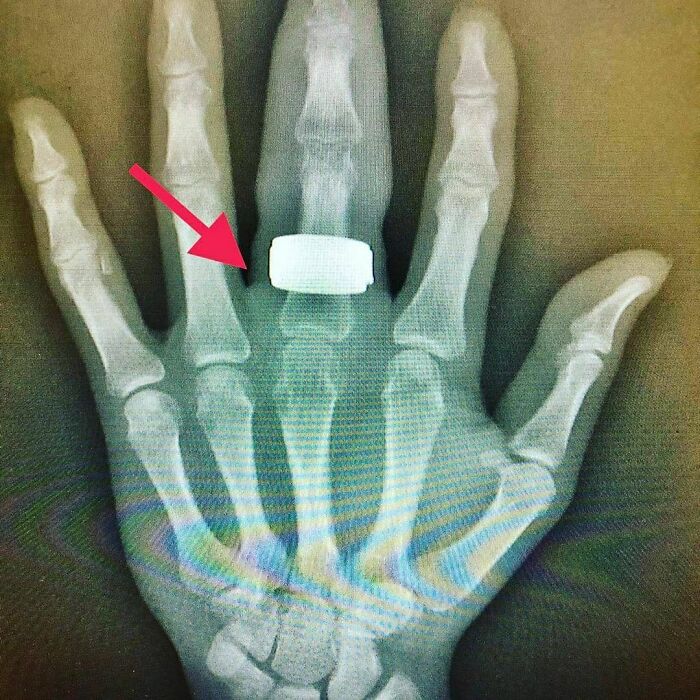

#73 A Ring Burried Underneath The Skin

Image credits: medicalpedia